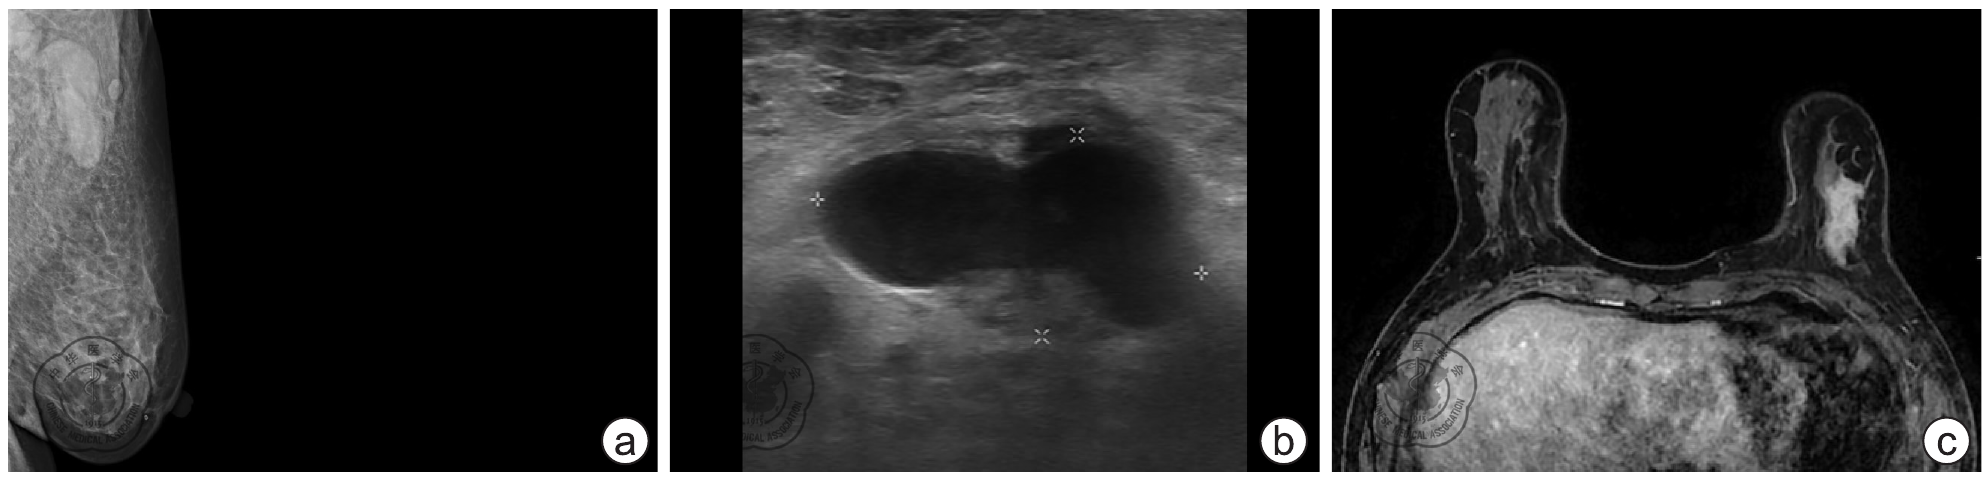

Mammography combined with ultrasonography versus MRI for diagnosis of breast cancer

To assess the diagnostic efficacy of mammography(MAM)combined with ultrasonography (US) and magnetic resonance imaging (MRI) for breast cancer.

The imaging data (including MAM, US and MRI) of 255 patients(260 breast lesions)with breast diseases in the Fourth Affiliated Hospital of Hebei Medical University from April 2015 to December 2016 were analyzed retrospectively. Pathological diagnosis of the lesions was set as the gold standard. The diagnostic results of MAM, US and MRI are classified according to BI-RADS and the lesions of BI-RADS grades 4 and 5 were regarded positive. The receiver operating characteristic (ROC) curve was used to evaluate the diagnosis performances of the two methods. Kappa test was used to evaluate the consistency of the two methods with the pathological results.

The sensitivity, specificity and accuracy of MAM combined with US for breast cancer diagnosis were 98.6%(204/207), 77.4%(41/53) and 94.2%(245/260), respectively. The sensitivity, specificity and accuracy of MRI were 98.1%(203/207), 66.0%(35/53) and 91.5%(238/260), respectively. With the pathological diagnosis as the gold standard, the Kappa value of MAM combined with US in consistency test was 0.810 (P<0.001), while the Kappa value of MRI was 0.711(P<0.001). The areas under ROC curves of MAM combined with US and MRI for the diagnosis of breast lesions were 0.902(95% CI: 0.843-0.961, P<0.001)and 0.893(95% CI: 0.842-0.945, P<0.001), indicating no significant difference (Z=0.050, P>0.050).

MAM combined with US and MRI both have high diagnostic accuracy for breast cancer, with equivalent diagnostic value. MAM combined with US is the first choice for breast cancer patients because of its simple operation and low cost, but the role of MRI in preoperative evaluation of breast cancer is irreplaceable.